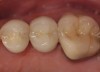

Core build-up was completed with Absolute Dentin™ (Parkell, www.parkell.com) dual-cure high-strength core composite. There are variations on color and how materials cure. For example, Light-Core™ (Bisco, www.bisco.com) is a light-cured blue material, Encore® (Centrix, www.centrixdental.com) is a self-cure white material, and Para Core (Coltène Whaledent, www.coltene.com) is a dual-cure white or dentin-colored material. Material was placed directly and light-cured for 40 seconds (Figure 9). Final preparation for a PFM was completed (Figure 10). The final crown was placed (Figure 11).

Figure 11  Final porcelain-fused-to-metal crown.

Figure 11